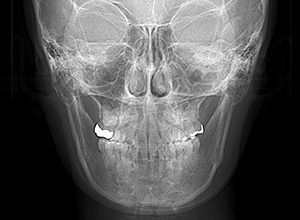

X-Ray

X-Ray所見

セファロ所見 下顎枝、骨体部共に大きくしっかりとしており下顎角は平均的であった。中顔面部の高さは高く奥行きあもり、上下顎骨は調和のとれた骨格形態をしていた。

パノラマ所見 右上8は埋伏していた。右下4根尖部付近にセメント質腫様所見が認められた。